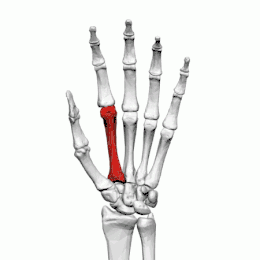

Deuxième métacarpien

Description

Le deuxième métacarpien est le plus long des métacarpiens.